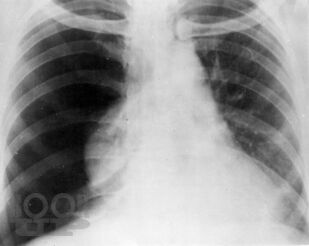

В руководстве представлены современные данные о механизмах развития наиболее частых неотложных заболеваний органов грудной и брюшной полостей, возникающие при них патологические изменения. Подробно изложены методы исследования, диагностики, общие принципы интенсивной терапии, основы предоперационной подготовки пациентов, показания к оперативным вмешательствам, техника их выполнения, принципы послеоперационного ведения больных. Третье издание руководства (второе вышло в 2006 г.) дополнено главами, посвященными неотложным состояниям и хирургической тактике при остро возникших гинекологических заболеваниях, а также получающему развитие методу видеоторакоскопии в неотложной торакальной хирургии.